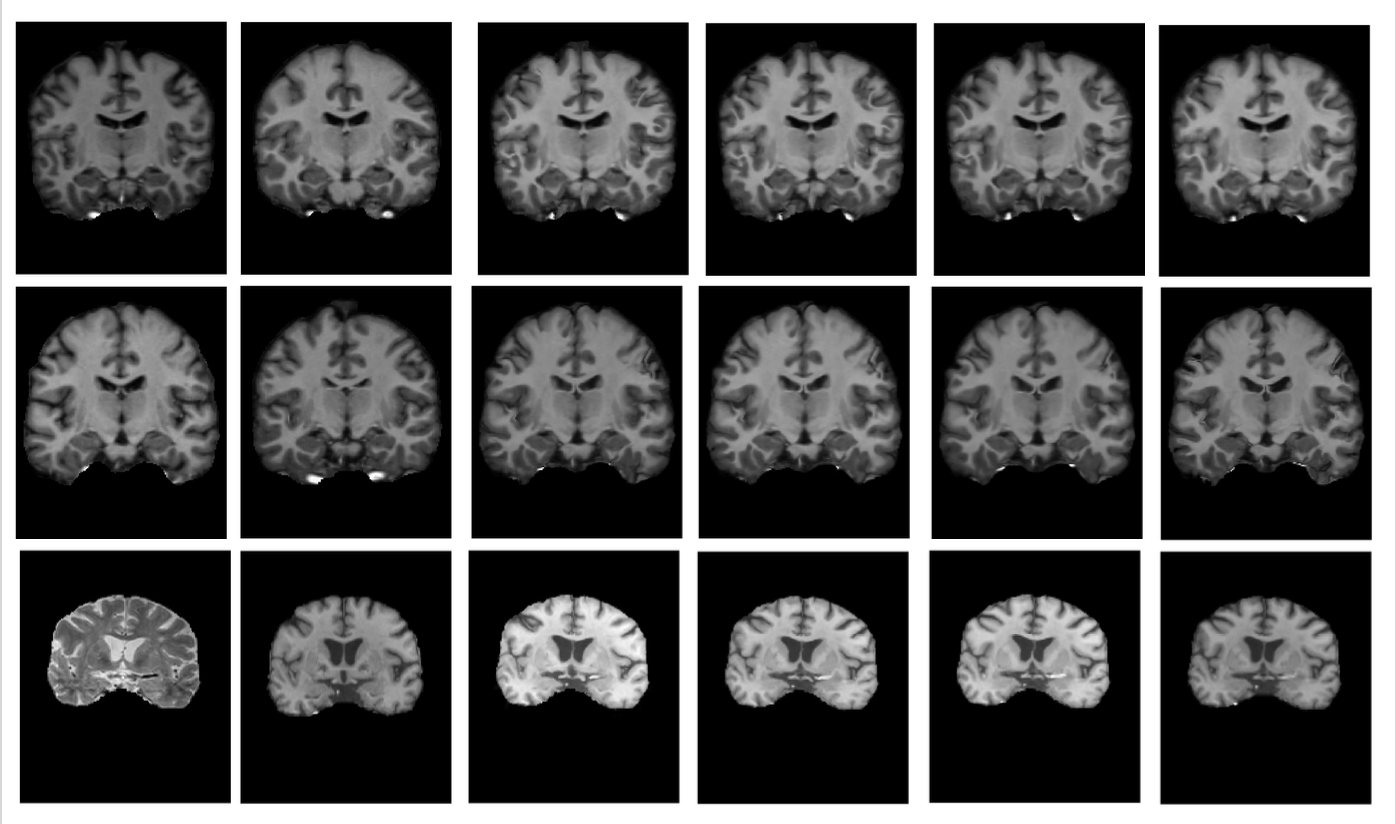

Qualitative Comparison: Figures 2(a) and 2(b) present example results for Total Variation (TV), Diffusion, Bending Energy, and the proposed DARE regularization across all datasets. The results are shown as deformed volumes and corresponding displacement grids, with folding areas highlighted by red boxes. These red boxes emphasize regions prone to folding, where DARE produces smoother and more plausible deformations compared to the other methods. This demonstrates DARE’s effectiveness in minimizing folding artifacts and generating realistic deformation fields across diverse datasets.

(a) Deformed volumes from the IXI (top), OASIS (middle), and MUI-P (bottom) datasets. From left to right: fixed image, moving image, results with total variation, diffusion, bending energy regularizers, and DARE.

(b) Displacement fields from the IXI (top), OASIS (middle), and MUI-P (bottom) datasets. From left to right: total variation, diffusion, bending energy regularizers, and DARE. Figure 2: Qualitative comparison of (a) deformed volumes and (b) displacement fields. -